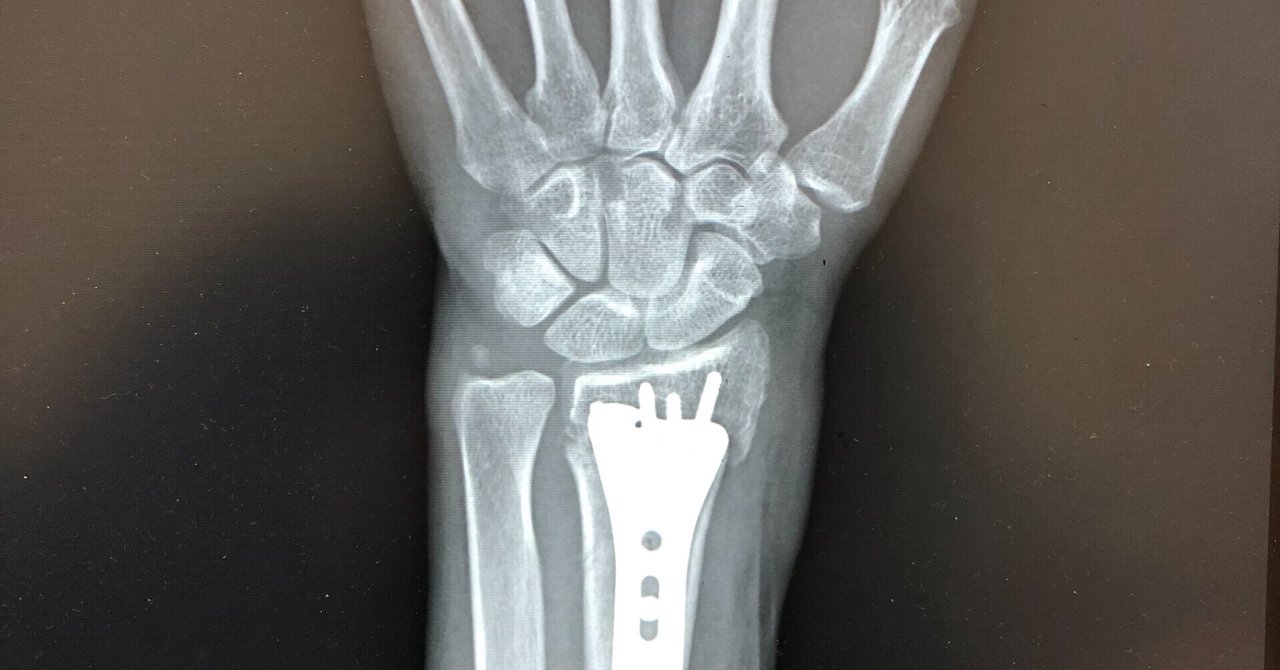

橈骨遠位端骨折 手術 健康ノート

橈骨遠位端骨折後のリハビリって何するの 怪我を予防するための 転ばぬ先の杖 がみっぷ物語

右手首骨折顛末 仙台通信note Sendaitribune Note